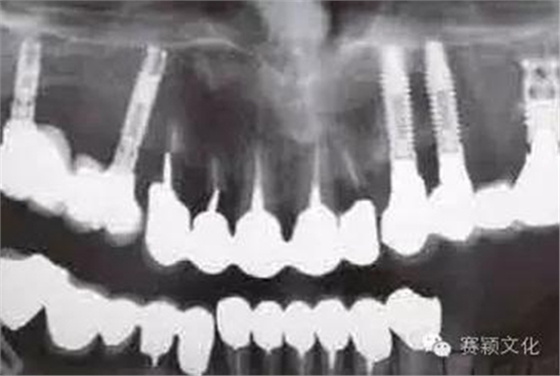

圖2 術(shù)前全景片

在某些特殊情況下,種植體需植入類骨質(zhì)(例如含BMP-2移植骨材料,密質(zhì)骨<15%)中,此時(shí)最好使用表面處理且粗糙的種植體。此處展示一應(yīng)用粗糙且表面處理的螺紋型種植體行拔牙位點(diǎn)的即刻種植(圖2~8)

圖8 術(shù)后X線片